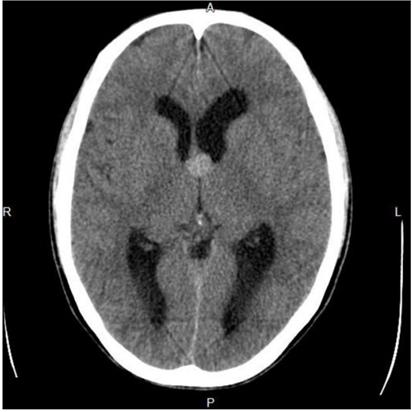

São lesões benignas que correspondem a 0,5% - 1% dos tumores cerebrais primários e a 15% - 20% das massas intraventriculares. Mais de 99% dessas lesões são encontradas no forame de Monro, tipicamente centradas no teto do terceiro ventrículo. A tomografia computadorizada (sem contraste venoso) abaixo é de um homem de 32 anos, previamente assintomático, com queixa atual de forte cefaleia há dois dias, e representa um caso típico destas lesões. Assinale a alternativa correta que contém o diagnóstico provável e complicações que podem ocorrer, até mesmo quando, a lesão tem pequenas dimensões.